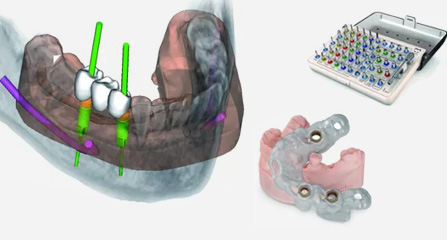

博愛牙科着眼于全鏈條的數字化診療解決方案,與德國Kavo、瑞典Nobel、韓國奧齒泰、中國康泰健等國際知名齒科品牌合作,建立“深圳數字化口腔聯盟”,應用全數字化口腔模式,從CBCT數據提取、AI口掃取模、AI智能口腔體檢、數字化分析模拟與方案設計、3D打印、CAD/CAM椅旁加工以及手術模拟導航等,全流程打通數字化口腔精确診療的各個環節,實現博愛數字化口腔診療體系新升級。

云端3D打印 导板精确辅助

动态导航监测 精确控制植入路径